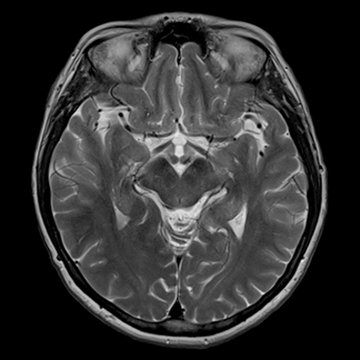

頭部ルーティーン

T2 TSE, matrix 512,